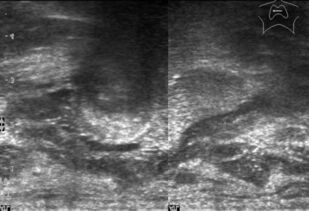

Ультразвуковое исследование оперированной щитовидной железы

В основу монографии положены материалы собственных исследований и практический опыт использования ультразвуковых методов диагностики при обследовании пациентов после хирургических вмешательств на щитовидной железе. Продемонстрированы диагностические возможности ультразвукового исследования в оценке состояния оперированной щитовидной железы в раннем и отдаленном послеоперационном периоде. Обобщена, систематизирована и представлена ультразвуковая семиотика зоны операции в ближайшие сроки после хирургических вмешательств и отражена динамика выявленных изменений. Убедительно показано, что ультразвуковое исследование может быть эффективным методом послеоперационного наблюдения.